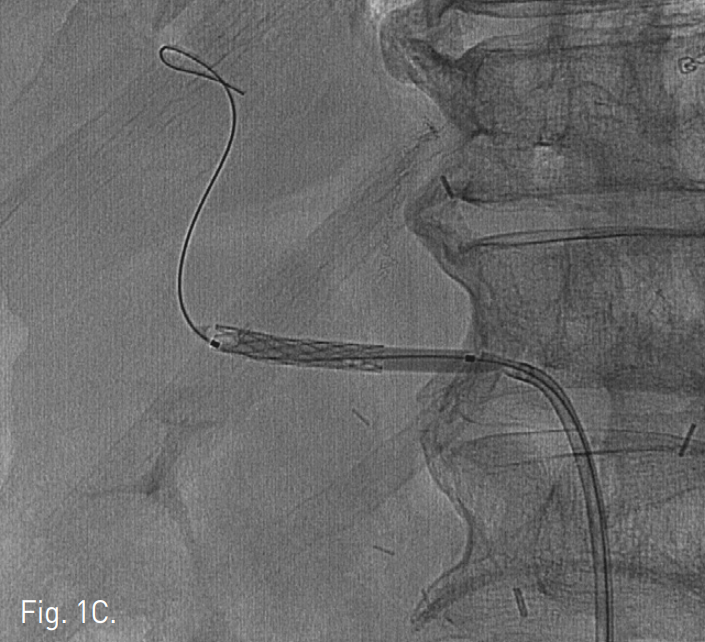

우측 대퇴동맥을 천자하여 복강동맥 조영술을 시행하여 가성동맥류의 크기와 위치를 확인하고 stent-graft를 설치하고자 하였다. 8F guiding catheter (Launcher, Medtronics Inc, Minneapolis)를 복강동맥 입구에 위치시키고 직경 4-9mm, 길이 28mm의 말초혈관용 stent graft(Jostent, Abbott, Germany) 를 직경 4mm, 길이 40mm balloon(Symmetry Balloon dilatation catheter, Boston Scientific, USA)에 장착하였다. 5F angiographic catheter와 0.035" guidewire로 좌측 간동맥을 selection한 후에 exchange guidewire(18 control Wire, Boston Scientific, USA)로 교체한 후 Balloon ex pandable stent graft를 간동맥에 설치하였다(Fig. 1C). 시술 직후 시행한 복강동맥 조영술에서 가성동맥류 부위의 간동맥이 stent-graft 설치 범위에 충분히 포함되었으며 조영제 누출은 보이지 않는다(Fig. 1D).

C. A stent graft (Jostent; 4-9mm in diameter and 28mm in length) was positioned across the common hepatic artery and a 4mm-diameter balloon catheter was inflated to expand thestent graft.